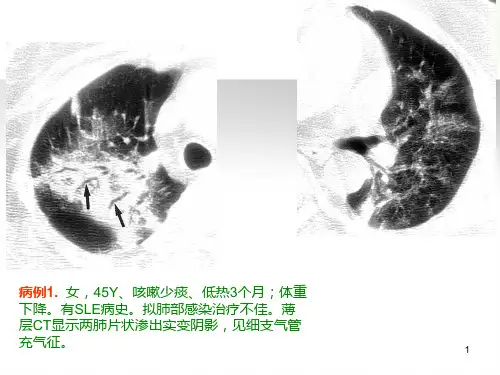

薄层